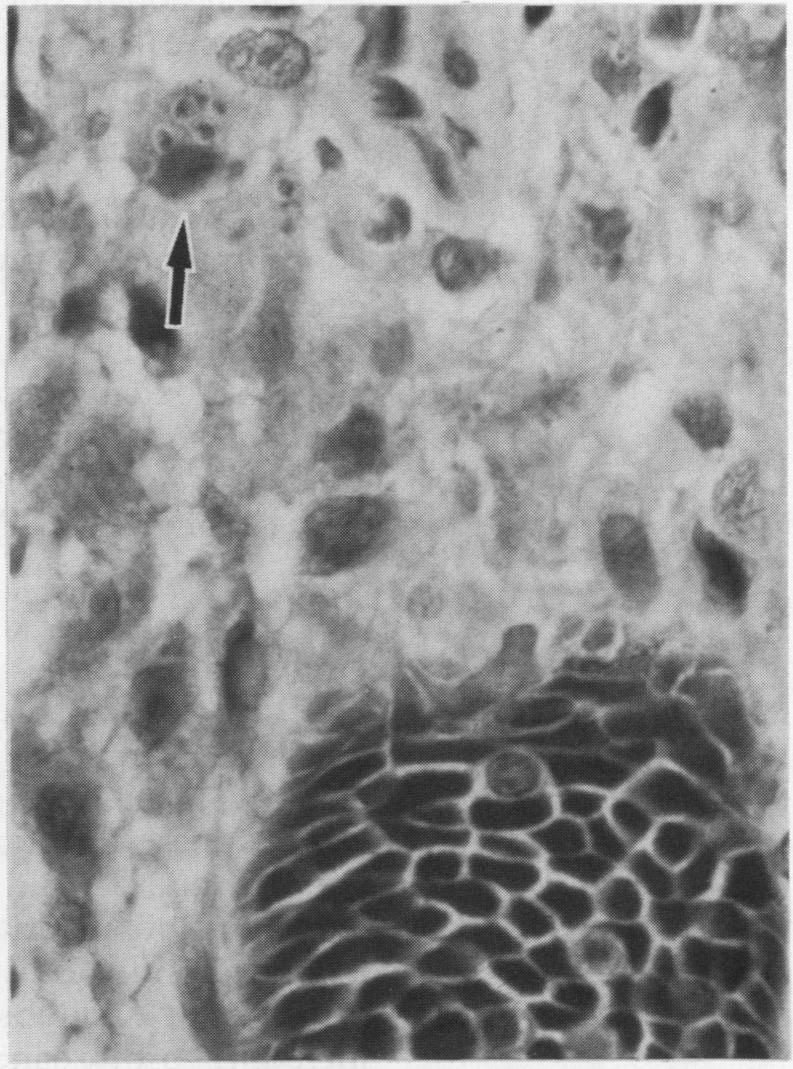

Opportunistic protozoan infections in human immunodeficiency virus disease: review highlighting diagnostic and therapeutic aspects.

摘要